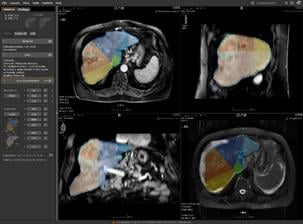

MRI is a vital imaging tool for the evaluation, assessment and management of the liver. CADstream’s liver application features include automated 3D image registration, segmentation (including whole organ, Couinaud-segments and lesion segmentation), kinetic and diffusion-weighted imaging analysis, patient monitoring comparisons and reporting. With CADstream, clinicians have a solution to automate analysis and standardize interpretation, ultimately achieving higher quality imaging studies, lower costs for radiology practices and improved communication for physicians and patients. Merge CAD will also showcase the latest in CADstream’s breast and prostate applications at RSNA 2009.